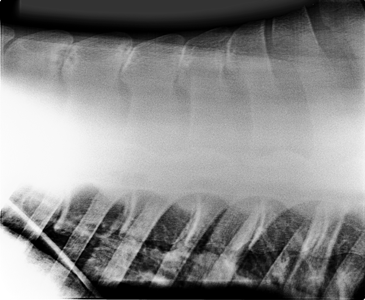

Het onderzoek wordt vervolgd door het maken van röntgenfoto’s van het pijnlijke gedeelte van de rug. Omdat er om de rug van een paard erg veel spieren zitten moeten de röntgenfoto’s gemaakt worden met behulp van een speciale cassettehouder, ook wel een buggy genoemd.

Op de röntgenfoto’s kunnen de benige structuren van de rug beoordeeld worden. Bij kissing spines staan de spinaaluitsteeksels (doornuitsteeksels) te dicht bij elkaar, soms overlappen ze zelfs. Ook kan je er artrose van de facet gewrichten in de rug of spondylose op beoordelen.